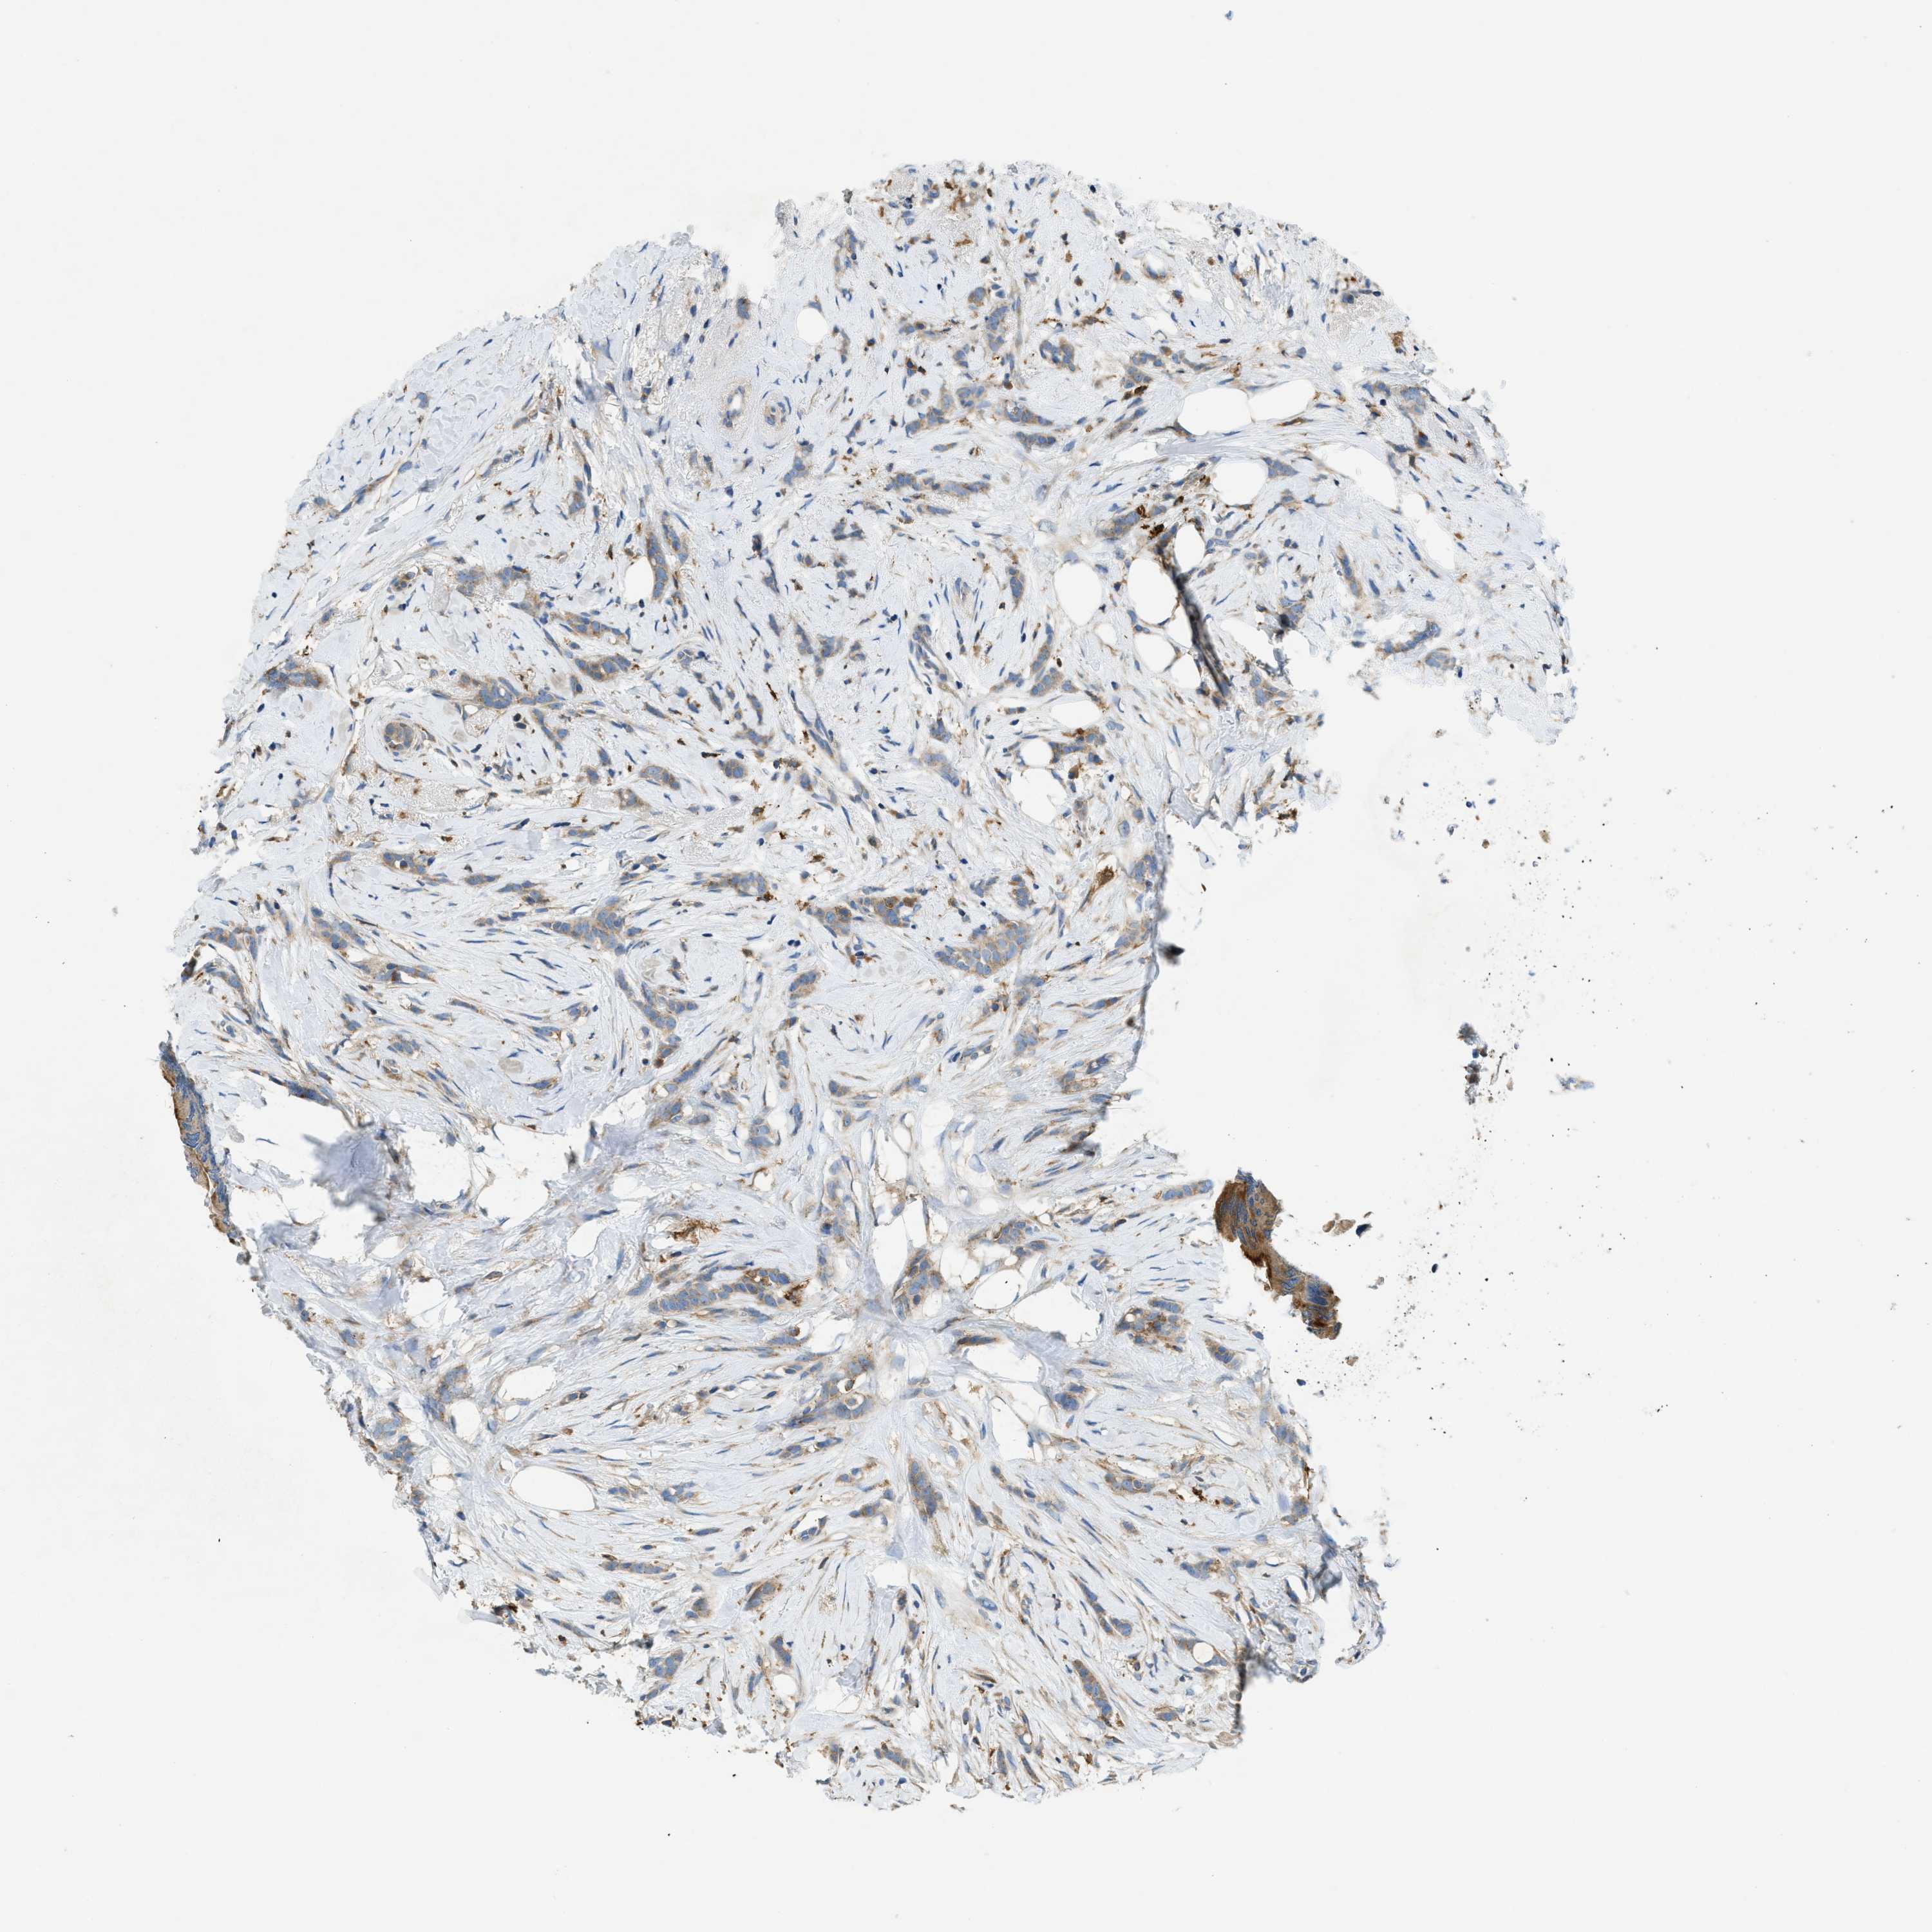

CANCER BREAST CANCER Show tissue menu

BRCA TCGA BRCA VALIDATION PROTEIN EXPRESSION

ANTIBODIES

AND

VALIDATION